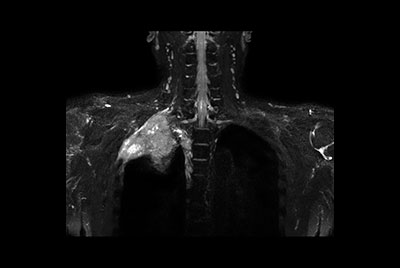

Brachial plexus tumor

Brachial Plexus with a hemangioma

Brachial Plexus lesion